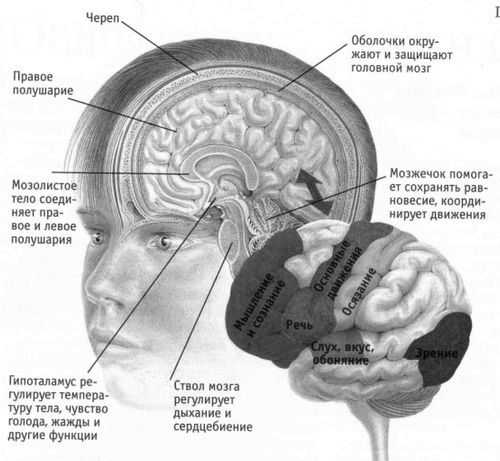

нейростімуляція - ще один спосіб боротьби із захворюванням. Процедура не є серйозним хірургічним втручанням і, що дуже важливо, не має протипоказань. Вона полягає в подачі на підведення електроди вище місця ураження електроімпульсів з необхідною напругою.

Ця процедура перешкоджає передачі імпульсів болю від нервових клітин до головного мозку і, тим самим, усуває біль.